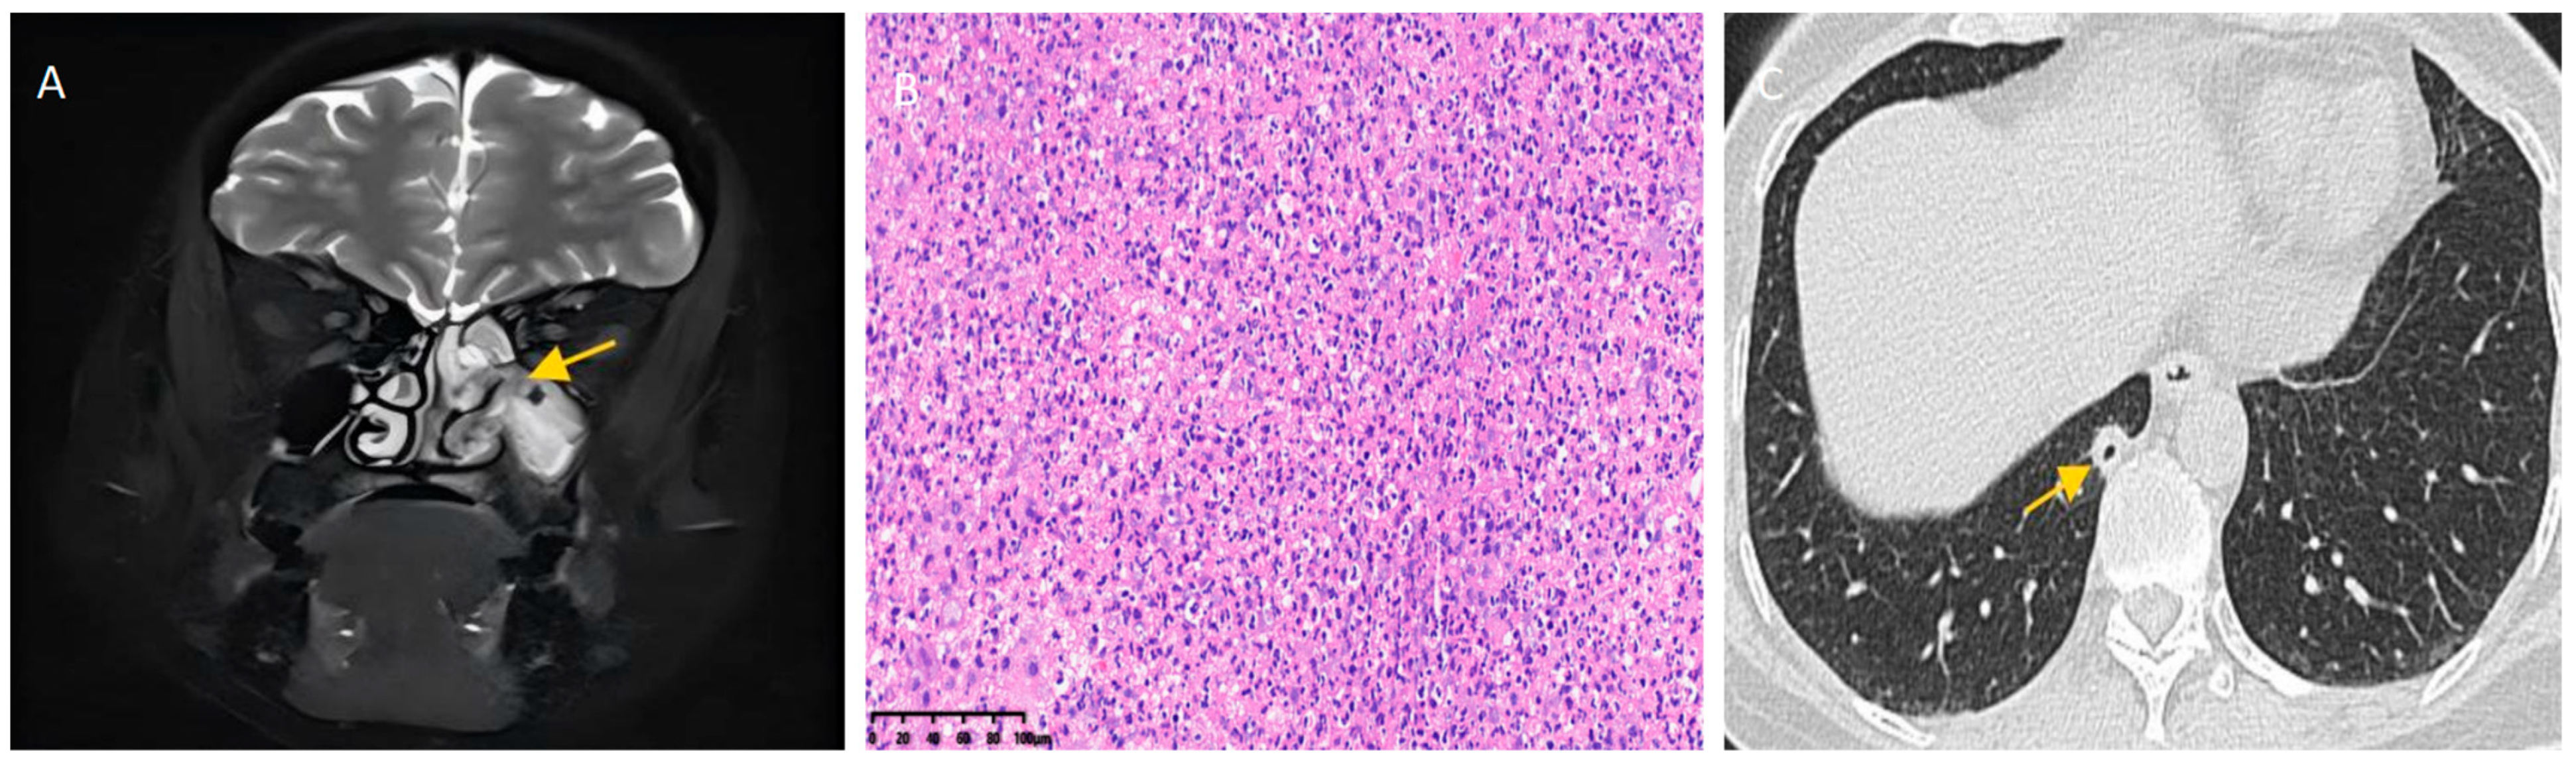

2. Report of a Case